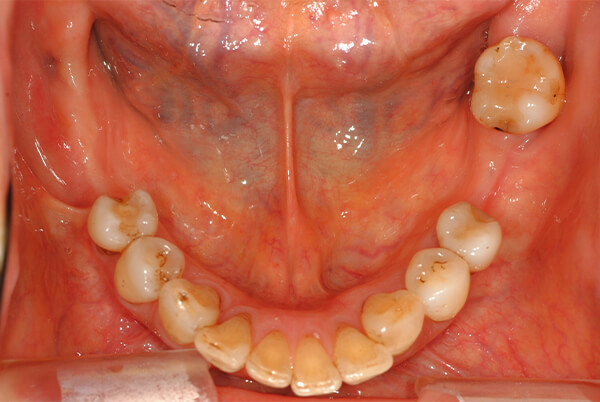

部分床義歯(Removable Partial Denture)

部分床義歯とは

残存している歯が有る場合の、欠損部分を補う着脱式の義歯のことを部分床義歯(部分入れ歯)といいます。歯が一本欠損している状態から一本残存している状態まで、口腔内の状態は様々なため、その状態に応じた適切な設計が肝要となります。

当院では保険適用の義歯はもちろん、保険適用外にはなりますが残存歯の保護に有効な2次再連結固定設計や、力学的な問題を劇的に改善するインプラントとのコンビネーション義歯など高度な義歯設計も行っています、既存の義歯にご不満がある方はぜひご相談ください。

1.レジン床部分義歯

保険適用で制作することができます。

強度を確保するためやや厚みがあります。